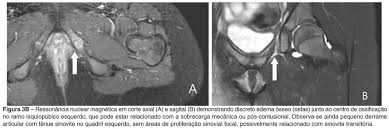

It is a temporary joint which is slimming to obliterate a bone fusion with skeletal maturation. Se observa un engrosamiento con edema óseo a nivel de la sincondrosis isquiopubiana derecha adyacente al músculo obturador externo flecha. The van Neck-Odelberg disease is hyperostosis of ischiopubic synchondrosis IPS.